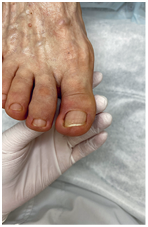

Иллюстрация к книге — Подология понятно. Важен каждый шаг. Справочник по проблемам подологии для клиентов и мастеров эстетики [i_277.jpg]

Девушка пыталась самостоятельно избавиться от мозоли с помощью мозольного пластыря с салициловой кислотой. Целостность кожного покрова была нарушена кислотами, входящими в состав пластыря. В рану попала инфекция и началось воспаление. Решали проблему с помощью хирурга.